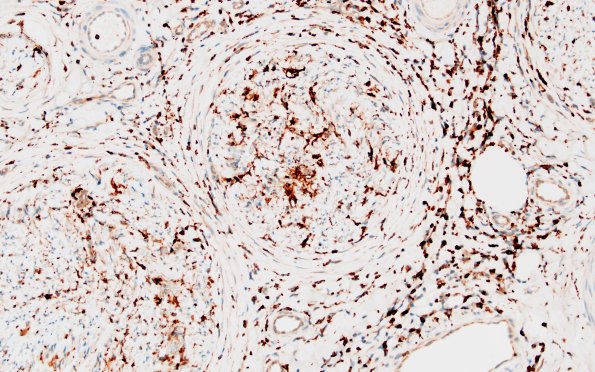

Washington University Experience | PERIPHERAL NEUROPATHY | 9B PERINEURITIS & PERINEURIAL PATHOLOGY | 1D2 Epineuritis & Perineuritis (Case 1) Immune checkpoint CD68 20X

Macrophages are numerous in the epineurium, perineurium and endoneurium but avoid large vessels. (CD68 IHC)